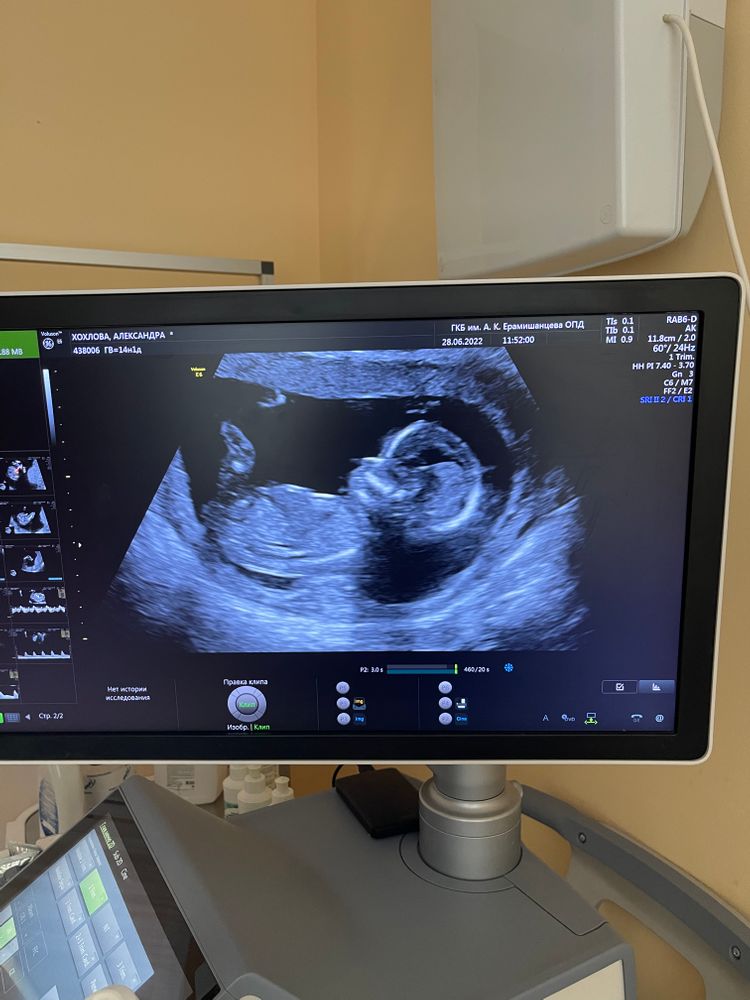

Пол на 14 неделях

Мы можем только гадать😁 А врач узист что-то сказал?))

Лена, узист вредный попался( Сказал что смотрят с 16 недели

Александра Хохлова, ну, на самом деле пол по узи можно увидеть реально на 2м скрининге только и то, если малыш не спрячет)) А на 1м скрининге это даже от врача лишь предположения, гарантии никто не даст)) Гарантированно на сроке от 10нед можно узнать пол лишь сдав кровь на ДНК (по НИПТ)